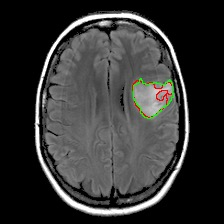

Neural processes have recently emerged as a class of powerful neural latent variable models that combine the strengths of neural networks and stochastic processes. As they can encode contextual data in the network's function space, they offer a new way to model task relatedness in multi-task learning. To study its potential, we develop multi-task neural processes, a new variant of neural processes for multi-task learning. In particular, we propose to explore transferable knowledge from related tasks in the function space to provide inductive bias for improving each individual task. To do so, we derive the function priors in a hierarchical Bayesian inference framework, which enables each task to incorporate the shared knowledge provided by related tasks into its context of the prediction function. Our multi-task neural processes methodologically expand the scope of vanilla neural processes and provide a new way of exploring task relatedness in function spaces for multi-task learning. The proposed multi-task neural processes are capable of learning multiple tasks with limited labeled data and in the presence of domain shift. We perform extensive experimental evaluations on several benchmarks for the multi-task regression and classification tasks. The results demonstrate the effectiveness of multi-task neural processes in transferring useful knowledge among tasks for multi-task learning and superior performance in multi-task classification and brain image segmentation.